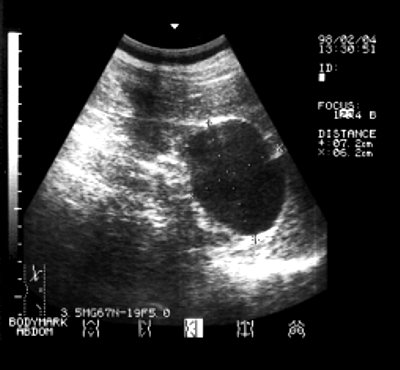

Врожденные кисты почек. Кисты одиночные или единичные (больные с поликистозом в исследование не включались), округлые, однокамерные, тонкостенные, анэхогенные образования с единичными эхопозитивными включениями, деформирующие структуры почки. Позади очага определяется полоса отражений повышенной интенсивности, наблюдается дистопия окружающих органов и тканей. Размеры неизмененного фрагмента почки нормальные или уменьшены. Васкуляризация почки деформирована, но интенсивность кровотока сохранена. Структуры ворот почки без видимых органических изменений, капсула органа в зоне контакта с очагом не изменена (рис.1).

а) Эхограммы врожденной кисты правой почки.

б) Остаточный очаг в правой почке через 3 года после склеротерапии кисты 96% этанолом.